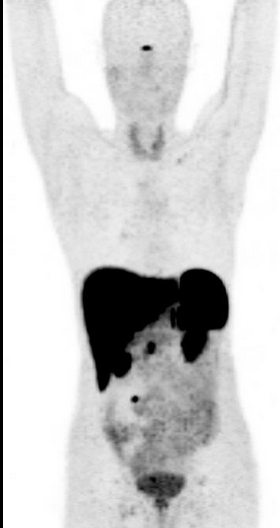

Normal Distribution of FDG-PET

• Highest uptake in brain

• Higher in gray matter

• White matter only has axons so no glucose transporters present and therefore lower uptake

• Low levels of uptake

• Blood vessels

• Salivary glands

• Lymph nodes

• Uptake in liver used as the background level of metabolism

• Spleen should be equal to or lower in level of uptake compared to the liver

• Kidney

• Will have high levels in collecting system

• If have kidney disease may not have any in collecting system